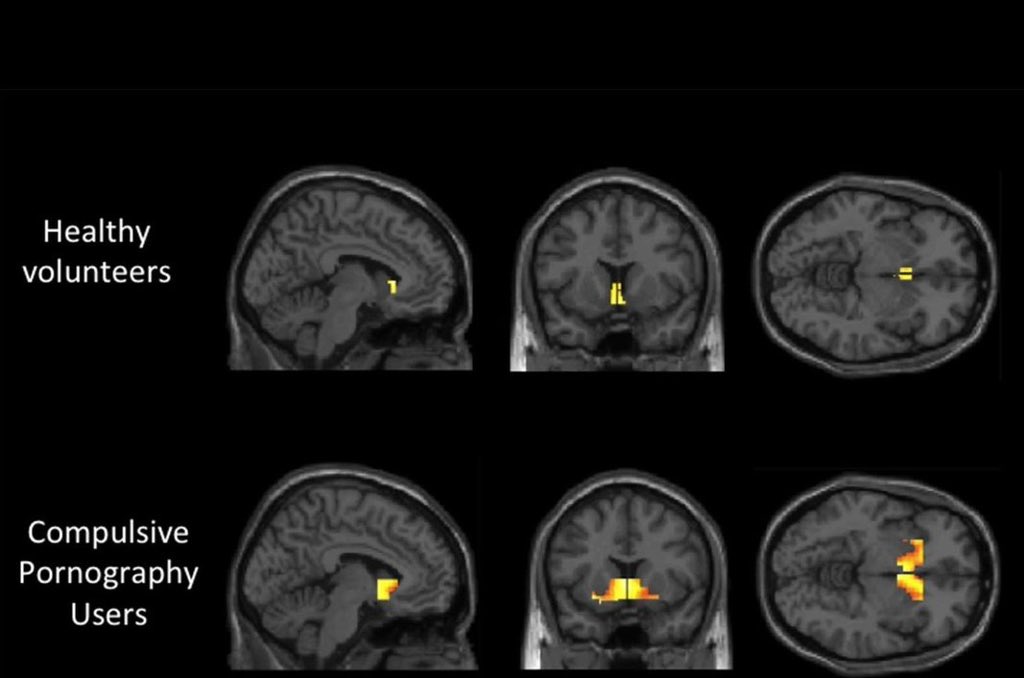

الإباحية تعيد تشكيل دماغك.